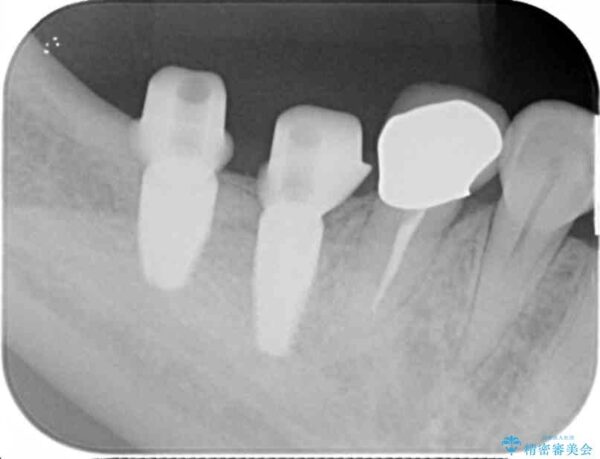

精査した結果、奥歯の根は破折しており抜歯を避けられない状況でした。

治療前

奥歯から膿のにおいがする インプラントによる機能回復 治療前画像 奥歯から膿のにおいがする インプラントによる機能回復 治療前画像 奥歯から膿のにおいがする インプラントによる機能回復 治療前画像 奥歯から膿のにおいがする インプラントによる機能回復 治療前画像 奥歯から膿のにおいがする インプラントによる機能回復 治療前画像 奥歯から膿のにおいがする インプラントによる機能回復 治療前画像

治療中

奥歯から膿のにおいがする インプラントによる機能回復 治療中画像 奥歯から膿のにおいがする インプラントによる機能回復 治療中画像 奥歯から膿のにおいがする インプラントによる機能回復 治療中画像 奥歯から膿のにおいがする インプラントによる機能回復 治療中画像